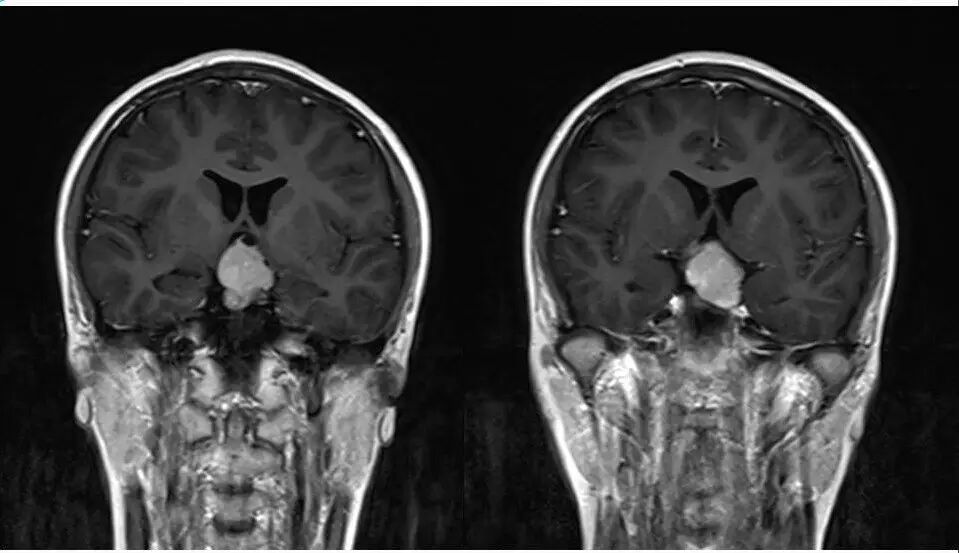

2.MR检查显示肿瘤位于鞍区,分叶状生长,呈稍长T2、稍长T1异常信号影,边界清楚,内部信号不均匀,其内可见“微囊”状异常信号影,视交叉受压上抬,DWI呈等或略高信号影,注药后呈不均匀明显强化;

4.重点观察冠状位:病变源于垂体偏左侧,与垂体界限不清楚,肿瘤偏右侧可见垂体与肿瘤之间裂隙,造成矢状位平扫及强化后误认为正常垂体存在,从而首先除外了垂体瘤,导致误诊;